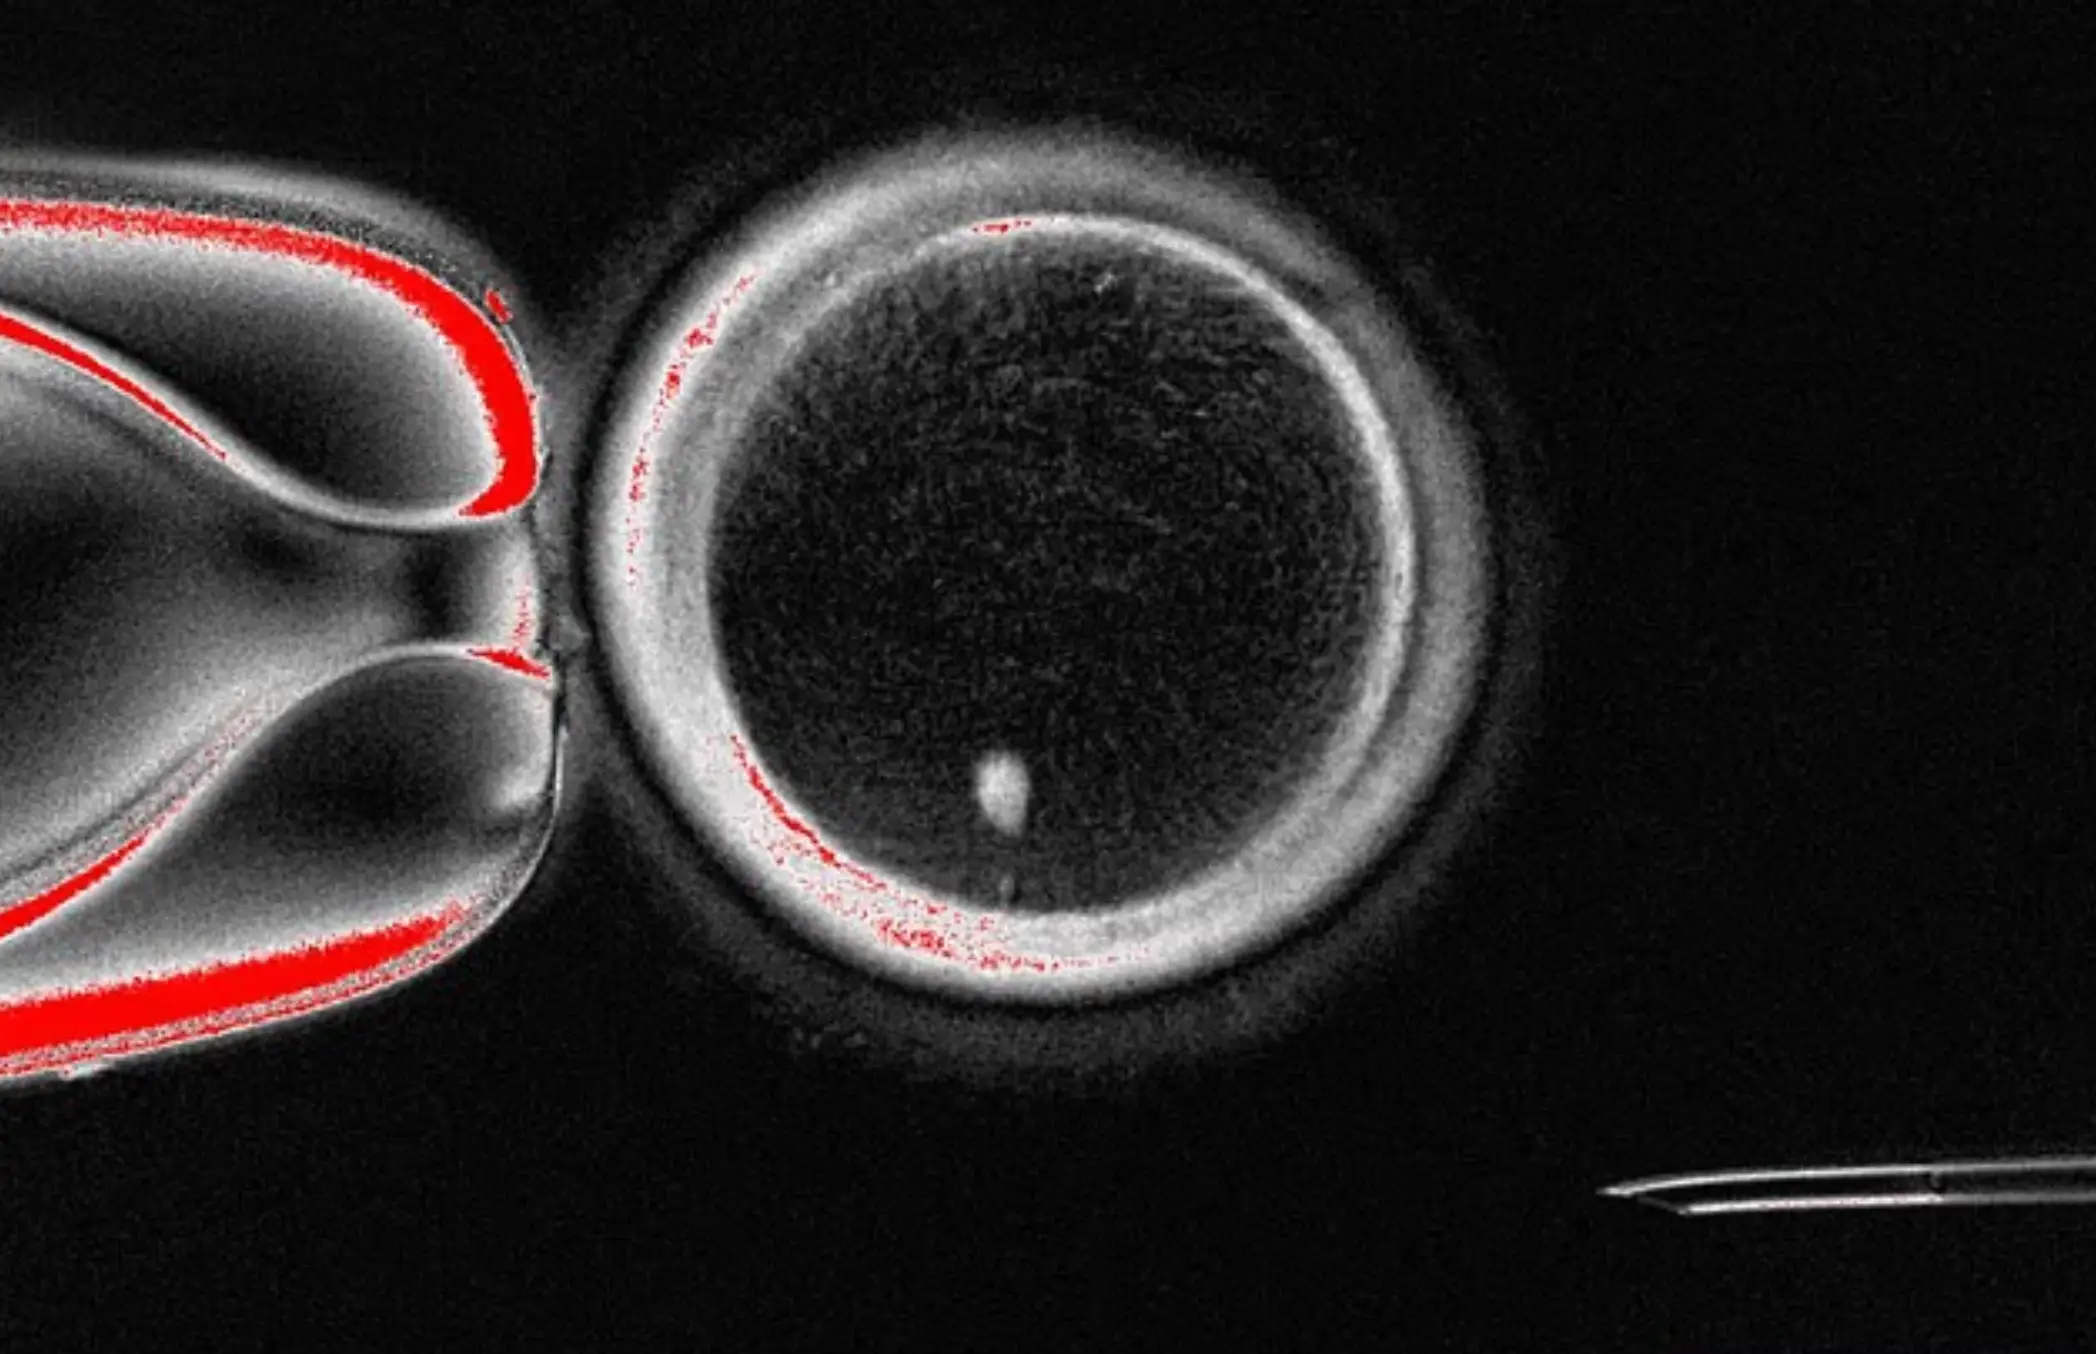

As for how this process works, the researchers extracted the nucleus, which contains the entire genetic code needed to construct a person's body, and placed it inside a donor egg that had had its genetic code removed, which is a similar technique that scientists have used to clone animals.

However, before being fertilised with a man's sperm, the egg must discard half of its 46 chromosomes. According to the study, 82 functional eggs were created and fertilised, eventually progressing to the six-day stage.